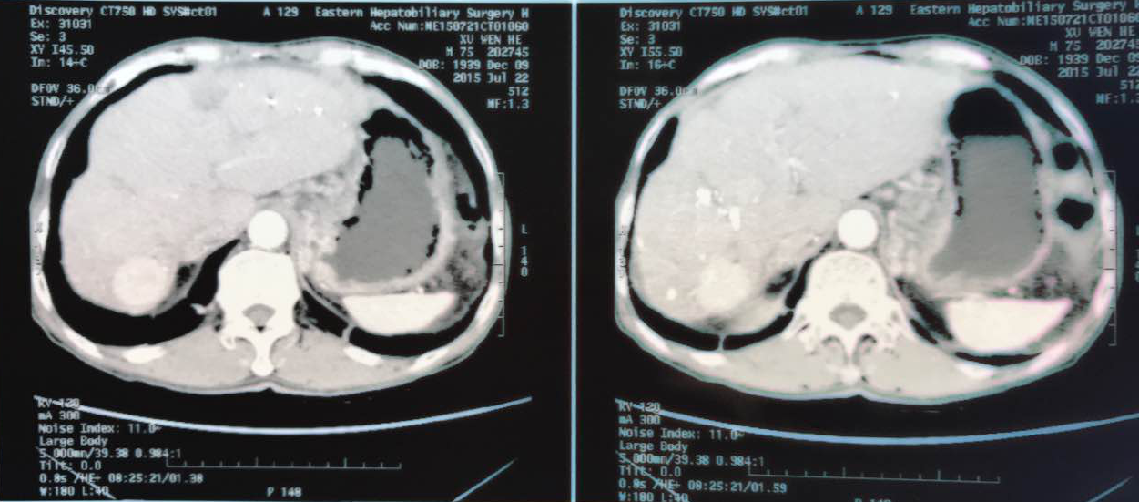

2015年7月发现右肝两复发结节,大的3cm,小的0.9cm。AFP7.1ug/L

超选左右肝以及右肝动脉注入碘油5ml,吡柔比星20mg,羟基喜树碱15mg,明胶海绵颗粒1/5。

图片12.png

图片13.png